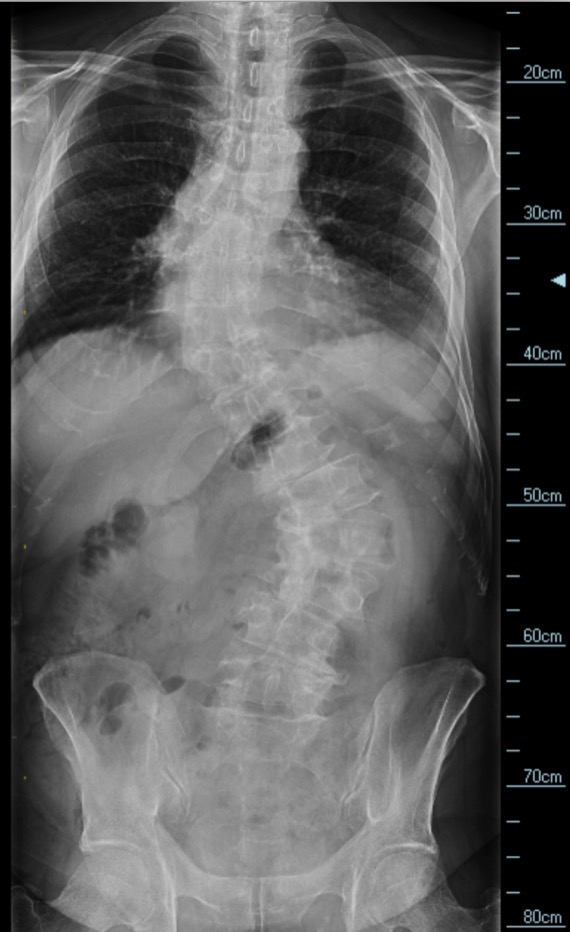

Included with my story are images of my first surgery on the neck and an image of my entire spine (to be repaired in late Spring).